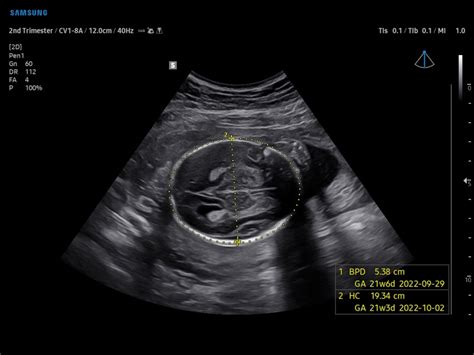

The IIIBPD, or Inner-to-Inner Biparietal Diameter , is a crucial measurement taken during ultrasound scans to assess fetal growth and estimate gestational age. Unlike the more commonly used BPD (Biparietal Diameter) which measures from the outer edge of one parietal bone to the outer edge of the other, the IIIBPD specifically measures the distance between the inner edges of these bones. This subtle difference aims to provide a more accurate and consistent measurement, reducing variability caused by differing skull thicknesses. Doctors and sonographers use this measurement to get a sense of how the baby’s head is developing, which is a key indicator of overall growth and neurological development. So why is this measurement so important? For starters, it helps confirm the estimated due date. The IIIBPD, when combined with other biometric measurements like HC, AC, and FL, paints a comprehensive picture of fetal development. If the IIIBPD falls outside the normal range for a particular gestational age, it could signal potential issues that need further investigation. These issues might include variations in head size, which could be related to genetic factors or other underlying conditions. However, it’s essential to remember that a single measurement outside the normal range doesn’t automatically indicate a problem. Doctors consider the overall growth pattern and other factors before making any conclusions. Regular monitoring and follow-up scans are often recommended to track the baby’s growth trajectory. In summary, the IIIBPD is a vital tool in fetal biometry, providing valuable information about fetal head growth and helping to ensure a healthy pregnancy. Its precise measurement technique minimizes variability, offering a more reliable assessment of fetal development. Remember, guys, that this measurement is just one piece of the puzzle, and your healthcare provider will consider all the information to provide the best possible care.

HC (Head Circumference): Measuring Your Baby’s Head